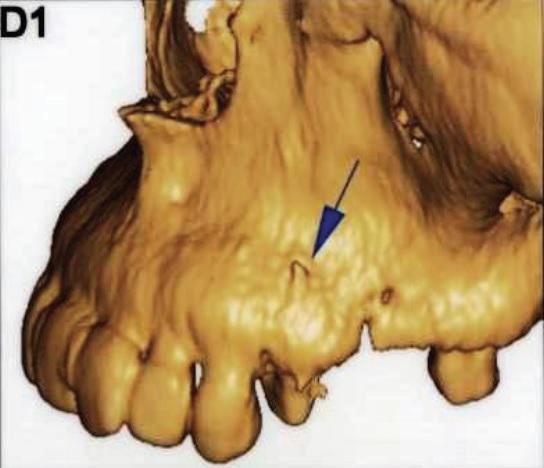

Полость корневых каналов промыли физиологическим раствором и восстановили зуб с помощью материалов для временного пломбирования. Чтобы предотвратить риск инфекции, в течение трех дней внутримышечно пациентке вводили клиндамицин (600 мг дважды в день), и также назначили ибупрофен (400 мг) для купирования боли, который она принимали по мере необходимости. Экстренное наружное использование холодных компрессов в первый день сменили на теплые компрессы во второй день для лечения отека. На первом повторном визите отмечалось увеличение кровоподтека, хотя припухлость значительно уменьшилась (фото 3). Отек и кровоподтек постепенно исчезали в течение всего периода наблюдения, а на 10 день после процедуры у пациентки исчезли все беспокоившие ее симптомы (фото 4). Для оценки соотношения между зубом, альвеолярным отростком и верхнечелюстной пазухой была проведена дентальная объемная томография (dental volumetric tomography — DVT) (NewTom 3G, QR SRL, Верона, Италия). На DVT-изображении было обнаружено, что апекс щечного корня перфорирует кортикальную пластинку верхнечелюстной кости, создавая, таким образом, свободный путь для проникновения ирригационного раствора в мягкие ткани (фото 5 (а) и фото 5 (б)). Через 10 дней симптомы полностью исчезли. В то же время в корневой канал наложили повязку с гидроксидом кальция. Во время заключительного посещения примерно через 4 недели после предыдущей процедуры корневые каналы запломбировали материалом AH Plus (Dentsply Maillefer) и гуттаперчей (фото 6).

Фото 5: (а) Изображение 3D и (б) коронарный вид DVT показали, что верхушка щечного канала перфорирует кортикальную пластинку верхней челюсти.

Большинство случаев выведения NaOCl за верхушку корня возникают вследствие неправильного определения рабочей длины инструмента, чрезмерного расширения апикального отверстия, боковых перфораций, заклинивания иглы в корневом канале или же вертикальных переломов корня. Деструкция альвеолярной кости в периапикальной области из-за присутствующих хронических инфекций, как и использование высокого давления во время инъекции только способствуют процессу экструзии NaOCl-ирриганта в окружающие мягкие ткани. В ходе анализа 23 случаев определено, что 18 пациентов были женщинами, а остальные 5 – мужчинами, 20 инцидентов случилось на верхней челюсти, и только 3 на нижней. Это можно объяснить тем, что зубы нижней челюсти расположены в центре более плотной кортикальной кости по сравнению с верхними зубами. Тонкий слой кортикальной пластинки внешне ограничивает область щечного корня премоляра верхней челюсти и остальных коренных зубов. Таким образом, зубы верхней челюсти более предрасположены к экструзии NaOCl в окружающие мягкие ткани по сравнению с зубами нижней челюсти. Behrents и коллеги также сообщили, что экструзия гипохлорита натрия возможна и при обработке корней второго премоляра верхней челюсти. На изображениях конусно-лучевой компьютерной томографии (КЛКТ) видно, что в данном клиническом случае верхушка щечного корня перфорировала кость верхней челюсти. Также в данном случае изображения DVT продемонстрировали, что существующая ранее периапикальная хроническая инфекция, как и перфорация верхнечелюстной кости верхушкой щечного корня, способствовали экструзии NaOCl. Кроме того, более чем вероятно, что врач применял избыточное давление при манипуляциях с ирригационной иглой или же иглу заклинивало в корневом канале, что также негативно повлияло на будущий прогноз неадекватной обработки канала. Более того, следует помнить, что в сомнительных случаях начальная томография может помочь определить возможные факторы риска, способствующие экструзии NaOCl.